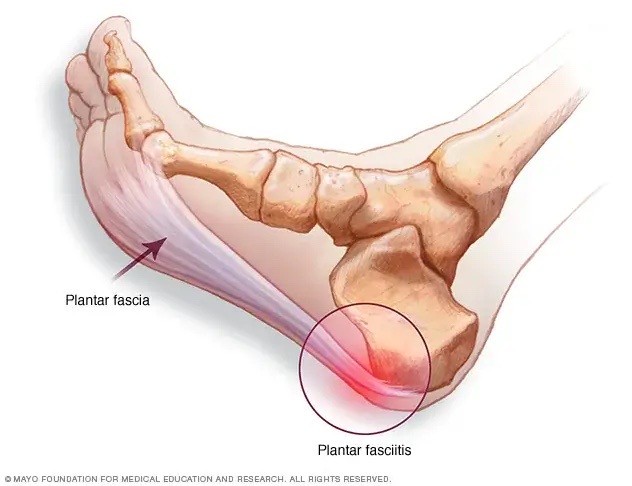

Especialidades

"Operar os dois pés e pisar imediatamente!” esse lema gerou resultados incríveis no tratamento do pé plano e do joanete. Conheça as técnicas que foram apresentadas pelo Dr Rodrigo Astolfi na Itália (pé plano) e na Coréia do Sul (joanete).